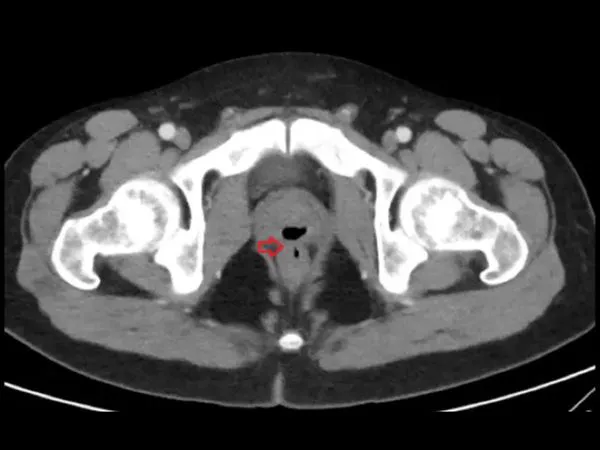

ಸಿಟಿ ಸ್ಕ್ಯಾನ್ ಮಾಡಿದಾಗ 'ಫಿಸ್ತುಲಾ' ಎಂಬ ಅನಿಲಭರಿತ ರಚನೆಯೊಂದು ಕಾಣಿಸಿಕೊಂಡಿದೆ. ಯುರೇತ್ರಾ ಹಾಗೂ ಗುದದ್ವಾರಗಳ ನಡುವೆ ಕಂಡುಬರುವ ಅಸಹಜ ನಾಳ ಈ ಫಿಸ್ತುಲಾ.